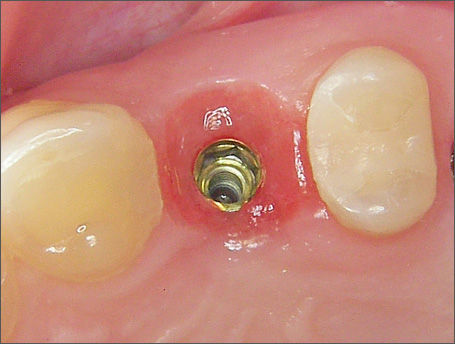

La morfologia convergente del collo Prama permette di recuperare la porzione di tessuto molle che con un impianto transmucoso tradizionale verrebbe occupata dal titanio del collo implantare. La convergenza di Prama fa sì che i volumi intorno alla porzione coronale dell’impianto vengano invece riempiti di coagulo e di importanti fattori di ricrescita, che si trasformano in tessuti molli spessi e funzionali.

L'ispessimento della gengiva che circonda il collo Prama rappresenta un beneficio indiscusso, soprattutto nei pazienti con biotipo più sottile, nei quali questo innovativo impianto apporta un ispessimento dei tessuti molli senza ricorrere a terapie rigenerative.

La stabilizzazione del connettivo, resa possibile dalla morfologia convergente e dalla microrigatura UTM, fa sì che tutto ciò che vi è al di sotto rimanga protetto e isolato da potenziali attacchi batterici, e che quindi l’osso si mantenga preservato in maniera efficace e a lungo, come ampiamente dimostrato dalla clinica.